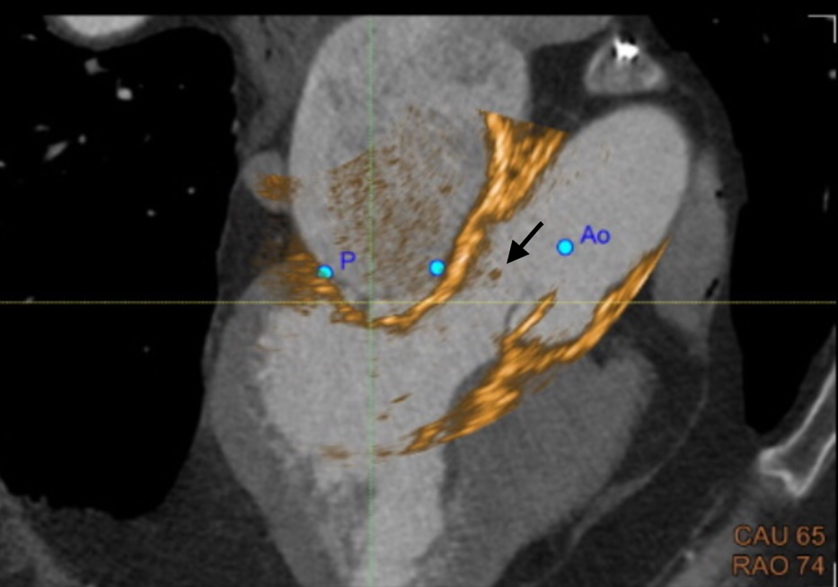

On the current presentation, the patient underwent repeat transthoracic echocardiography with bubble study and contrast-enhanced transthoracic echocardiography, neither of which demonstrated an intracardiac shunt or left ventricular thrombus. Electrocardiographically (ECG) synchronized cardiac computed tomography angiography (cCTA) was then performed as the final diagnostic test, supported by recent evidence demonstrating a higher diagnostic yield than echocardiography in the evaluation of acute stroke (Rinkel et al., 2022). cCTA revealed a 2-mm low-density tissue excrescence arising from the noncoronary cusp of the aortic valve (Figure 1) and simultaneously confirmed the absence of intracardiac thrombus or patent foramen ovale. Guided by cCTA localization, a repeat TEE with three-dimensional (3D) multiplanar reconstruction (Figure 2) successfully visualized the lesion. Intraoperative four-dimensional (4D) TEE with CT fusion—an innovative multimodality integration not previously described for this indication—was subsequently used for precise leaflet localization (Figures 3 and 4). Surgical pathology (Figure 5) demonstrated fibrocalcific degenerative changes of the noncoronary cusp and a small papillary fibroelastoma (PFE), which was deemed the most likely source of the patient’s recurrent cerebrovascular events.

Papillary fibroelastomas, although histologically benign, remain an important and often underrecognized cause of cardioembolic stroke, particularly when small, mobile, and located on left-sided valves. In this case, standard diagnostic evaluation failed to identify an embolic source. Electrocardiographically synchronized cardiac CTA ultimately revealed a subtle 2-mm excrescence on the noncoronary cusp of the aortic valve, which was subsequently confirmed via targeted three-dimensional multiplanar TEE and intraoperative four-dimensional (4D) TEE with CT fusion. Surgical excision demonstrated papillary fibroelastoma on pathology, and the patient has remained stroke-free on follow-up.